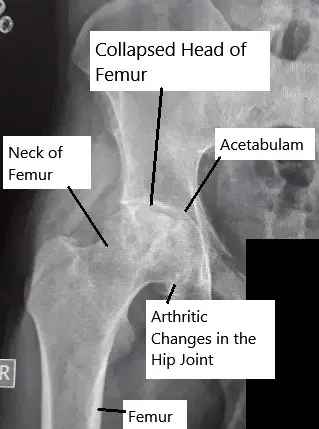

• X-ray showing avascular necrosis of the hip joint

Necrosis avascular

La necrosis avascular (NVA), también llamada osteonecrosis, es una enfermedad en la que el tejido óseo muere debido a un…